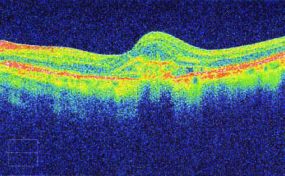

Optical Coherence Tomography uses low intensity infra-red light to give a 3D image of the back of the eye. It shows not only the surface but also the depth of the structures. It is similar to using ultrasound and creates an image not unlike an MRI or CT scan.

The instrument is incredibly good at measuring and monitoring Macular Degeneration. It can measure the thickness of the optic nerves which are affected by Glaucoma (and compare to an age, gender and ethnically matched normal).

In both circumstances it can mathematically show any changes from one visit to the next, working at a level way beyond the ability of even the most experienced observer with normal viewing methods.